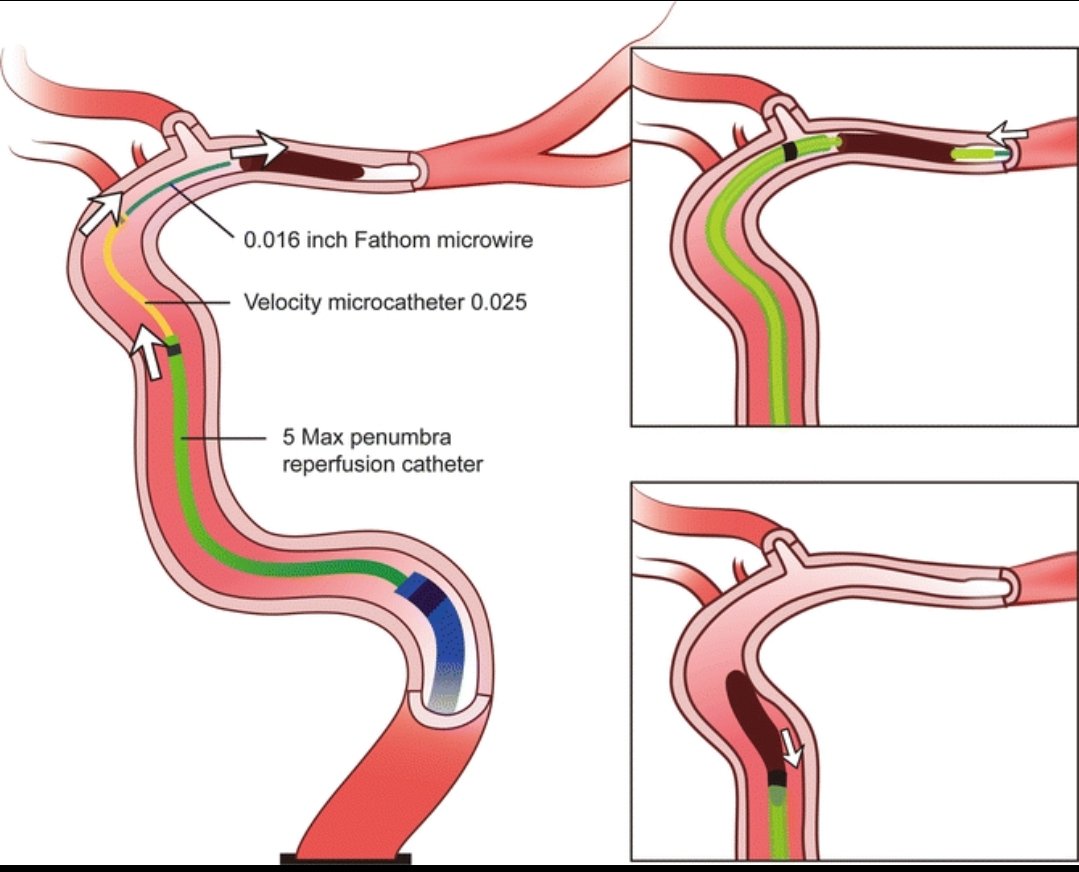

♦️قسطرة تداخليه لسحب الجلطه من الشرايين الرئيسيه ان وجدت

(فقط اول ٦ ساعات قد تمتد بشروط)

♦️قسطرة تداخليه لسحب الجلطه من الشرايين الرئيسيه ان وجدت

(فقط اول ٦ ساعات قد تمتد بشروط)

🧠عملية القسطرة التي يمكن إجراءها

♦️اول ٦ ساعات♦️من ظهور الأعراض

🧠عملية القسطرة التي يمكن إجراءها

♦️اول ٦ ساعات♦️من ظهور الأعراض